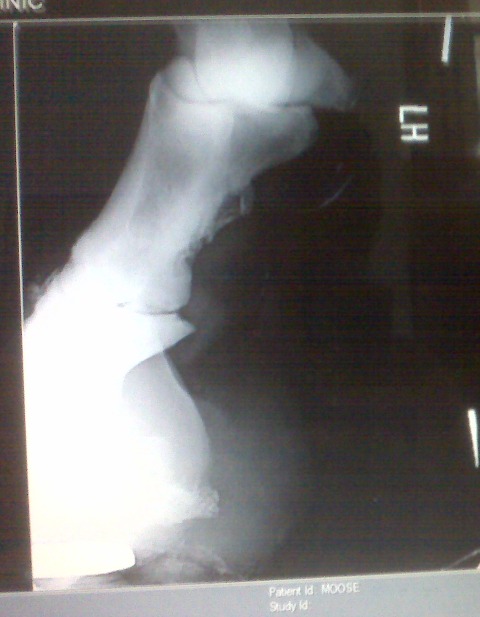

Posted on Sunday, Jun 27, 2010 - 10:00 am: Here are his x-rays that were taken 9/2007. It looks like references I have looked up as ringbone, what do you think?![]() ![]() ![]()

Posted on Tuesday, Jun 29, 2010 - 1:45 pm: Talk about a picture being worth a thousands words! Melissa your horse is not suffering so much from sidebone but has ringbone. This is a periostitis of the bones of the pastern that is spreading into the pastern joint (osteoarthritis) as evidenced by the osteophytes on the distal long pastern bone and proximal short pastern bone. By all means review the article on ringbone at HorseAdvice.com » Diseases of Horses » Lameness » Diseases of the Lower Limb » Ringbone. If you have questions following the article come back you can post them there and I will move this discussion into your post for continuities sake.DrO |